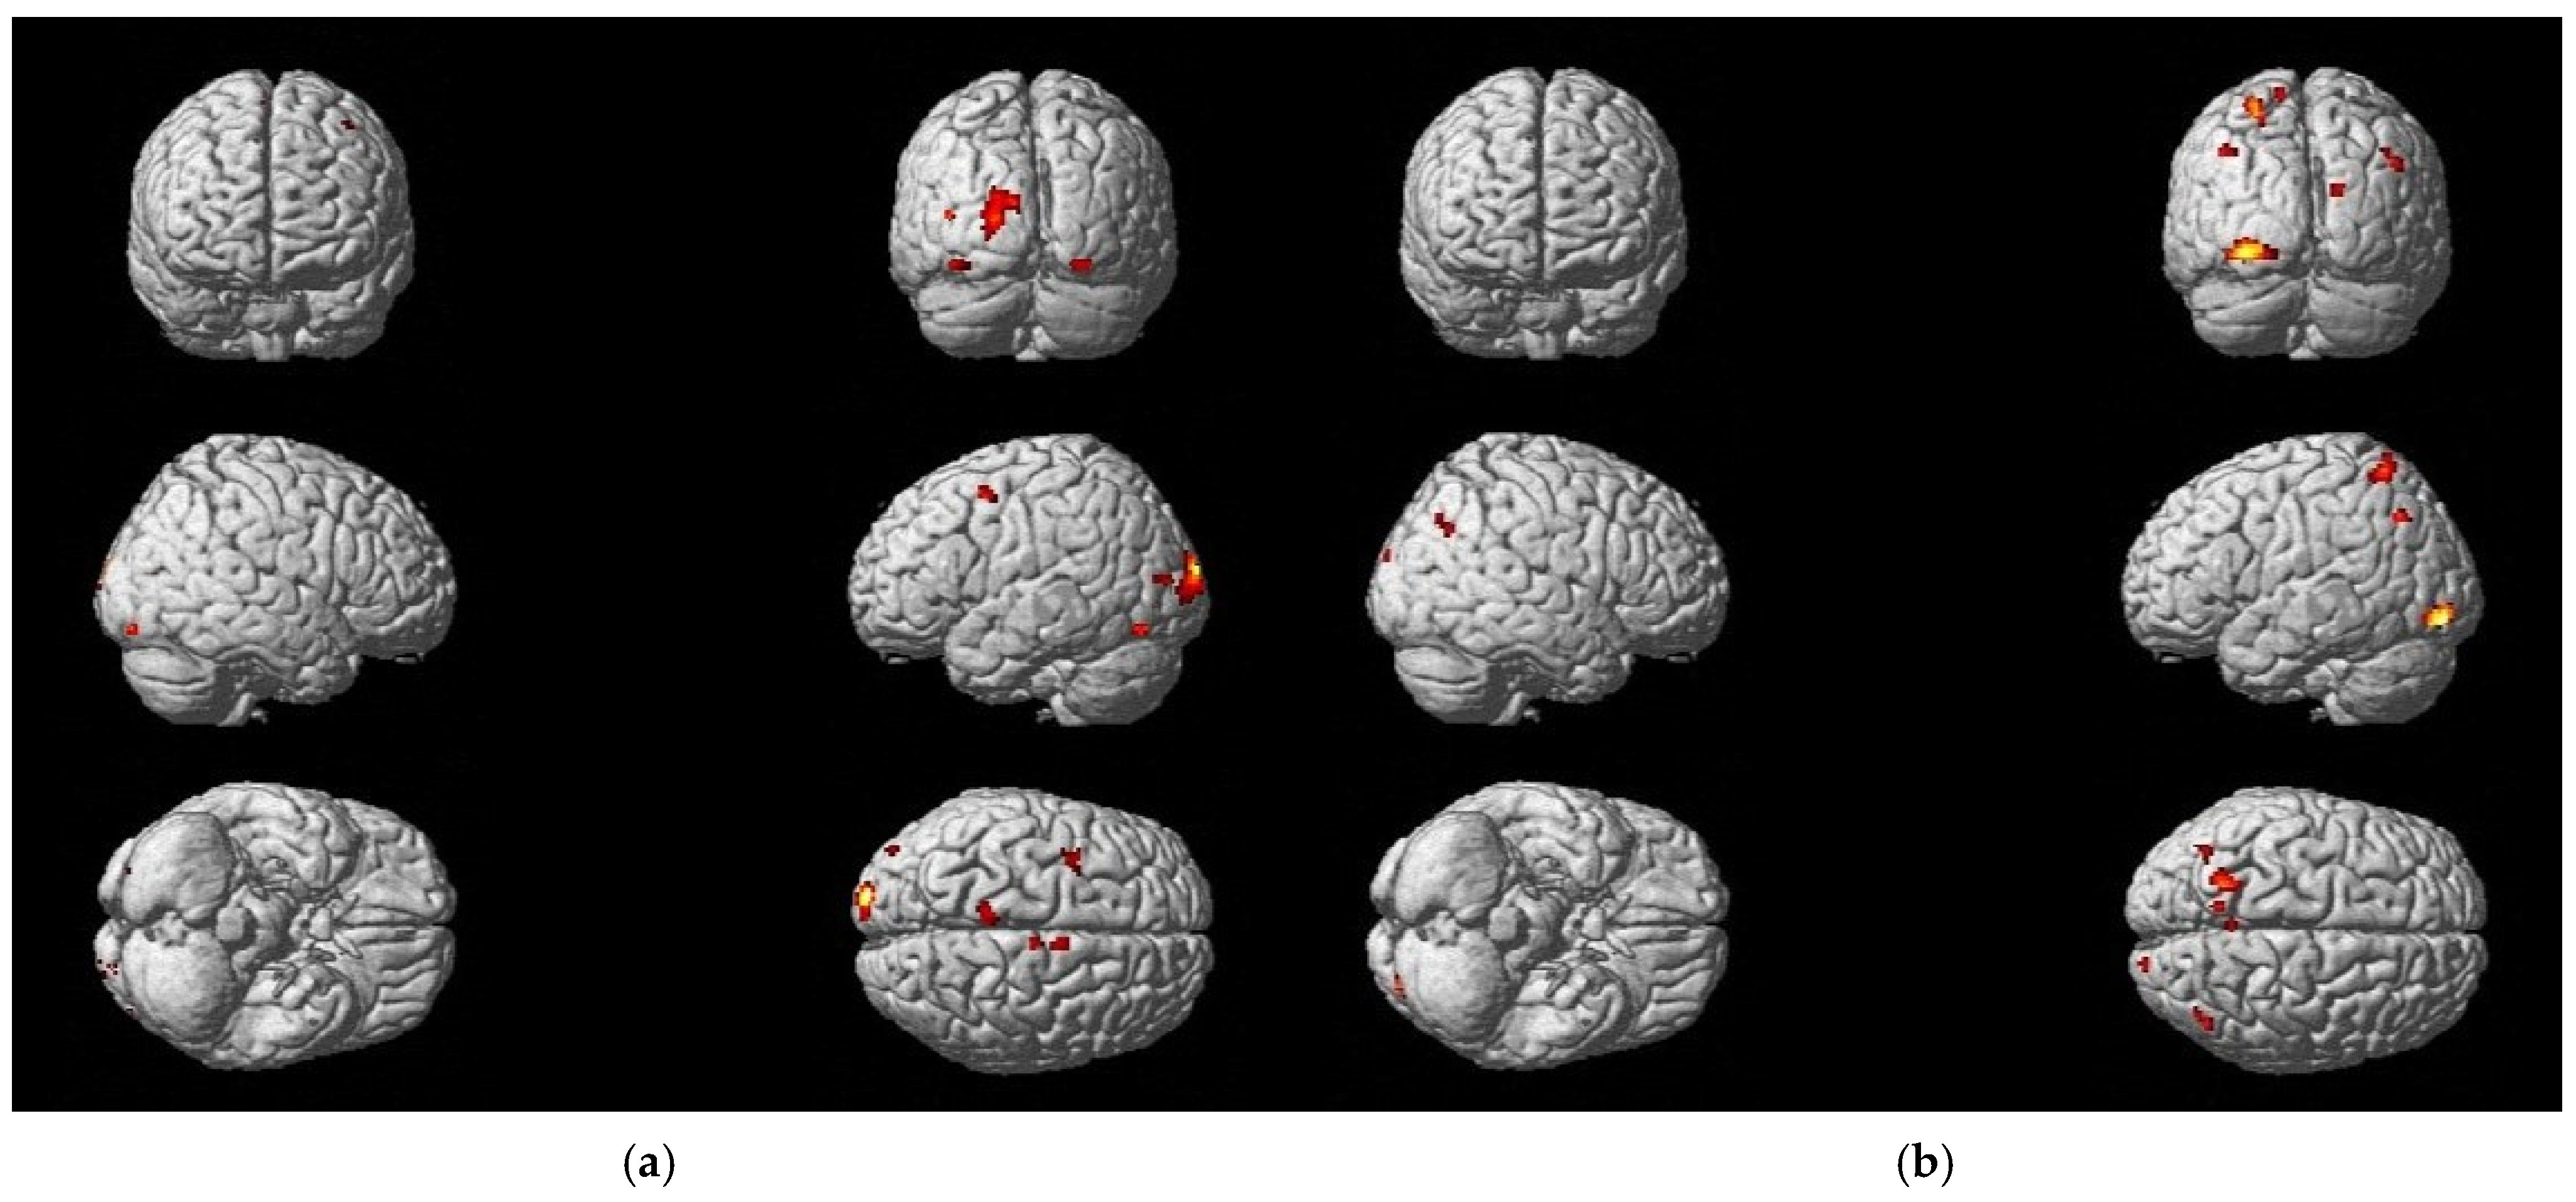

3.3. Differences in Activation Due to Treatment Methods